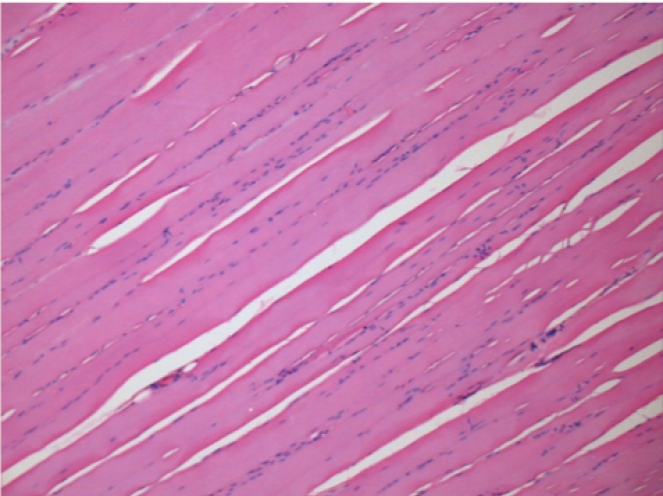

0,5 мл (5x 0,1 мл) підшкірна ін'єкція Ендопіл в праву підшкірну претибіальну ділянку.

Л:200x-Контроль-ПШ

П-10днів-ПШ-200X

П-30днів-ПШ-200X

П-90днів-ПШ-200X

П-210днів-ПШ-200X

П-210днів-ПШ-400X